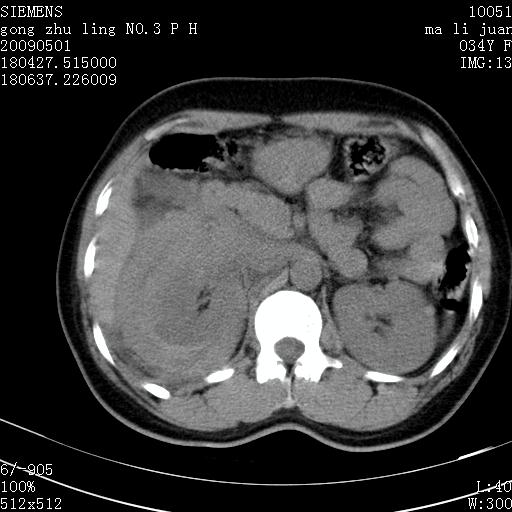

标题: CT19733:右肾碎裂

青年女性,骑摩托车摔伤。

右肾碎裂伤,包膜下血肿。

术中仅见右肾碎裂,肾蒂血管未见断裂。

支持 右肾破裂伴肾包膜下及肾周血肿。

右肾破裂并右侧腹膜后间隙出血。